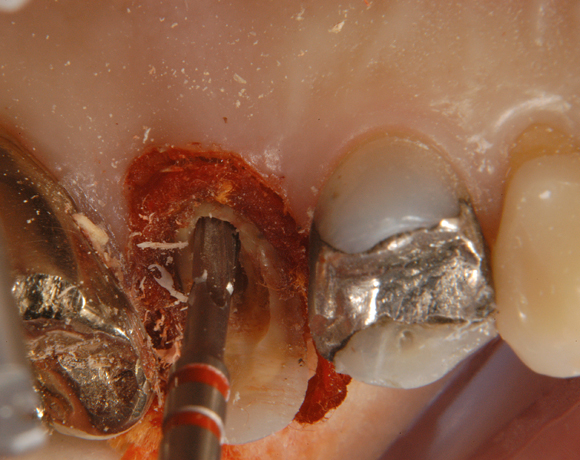

Ein Projekt aus dem Jahr 2003